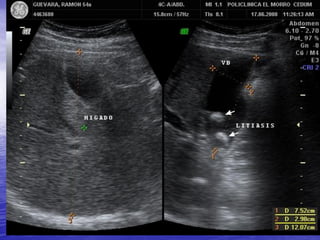

PATOLOGIA BILIAR

LITIASIS VESICULAR

OBSTRUCCION POR LITIASIS